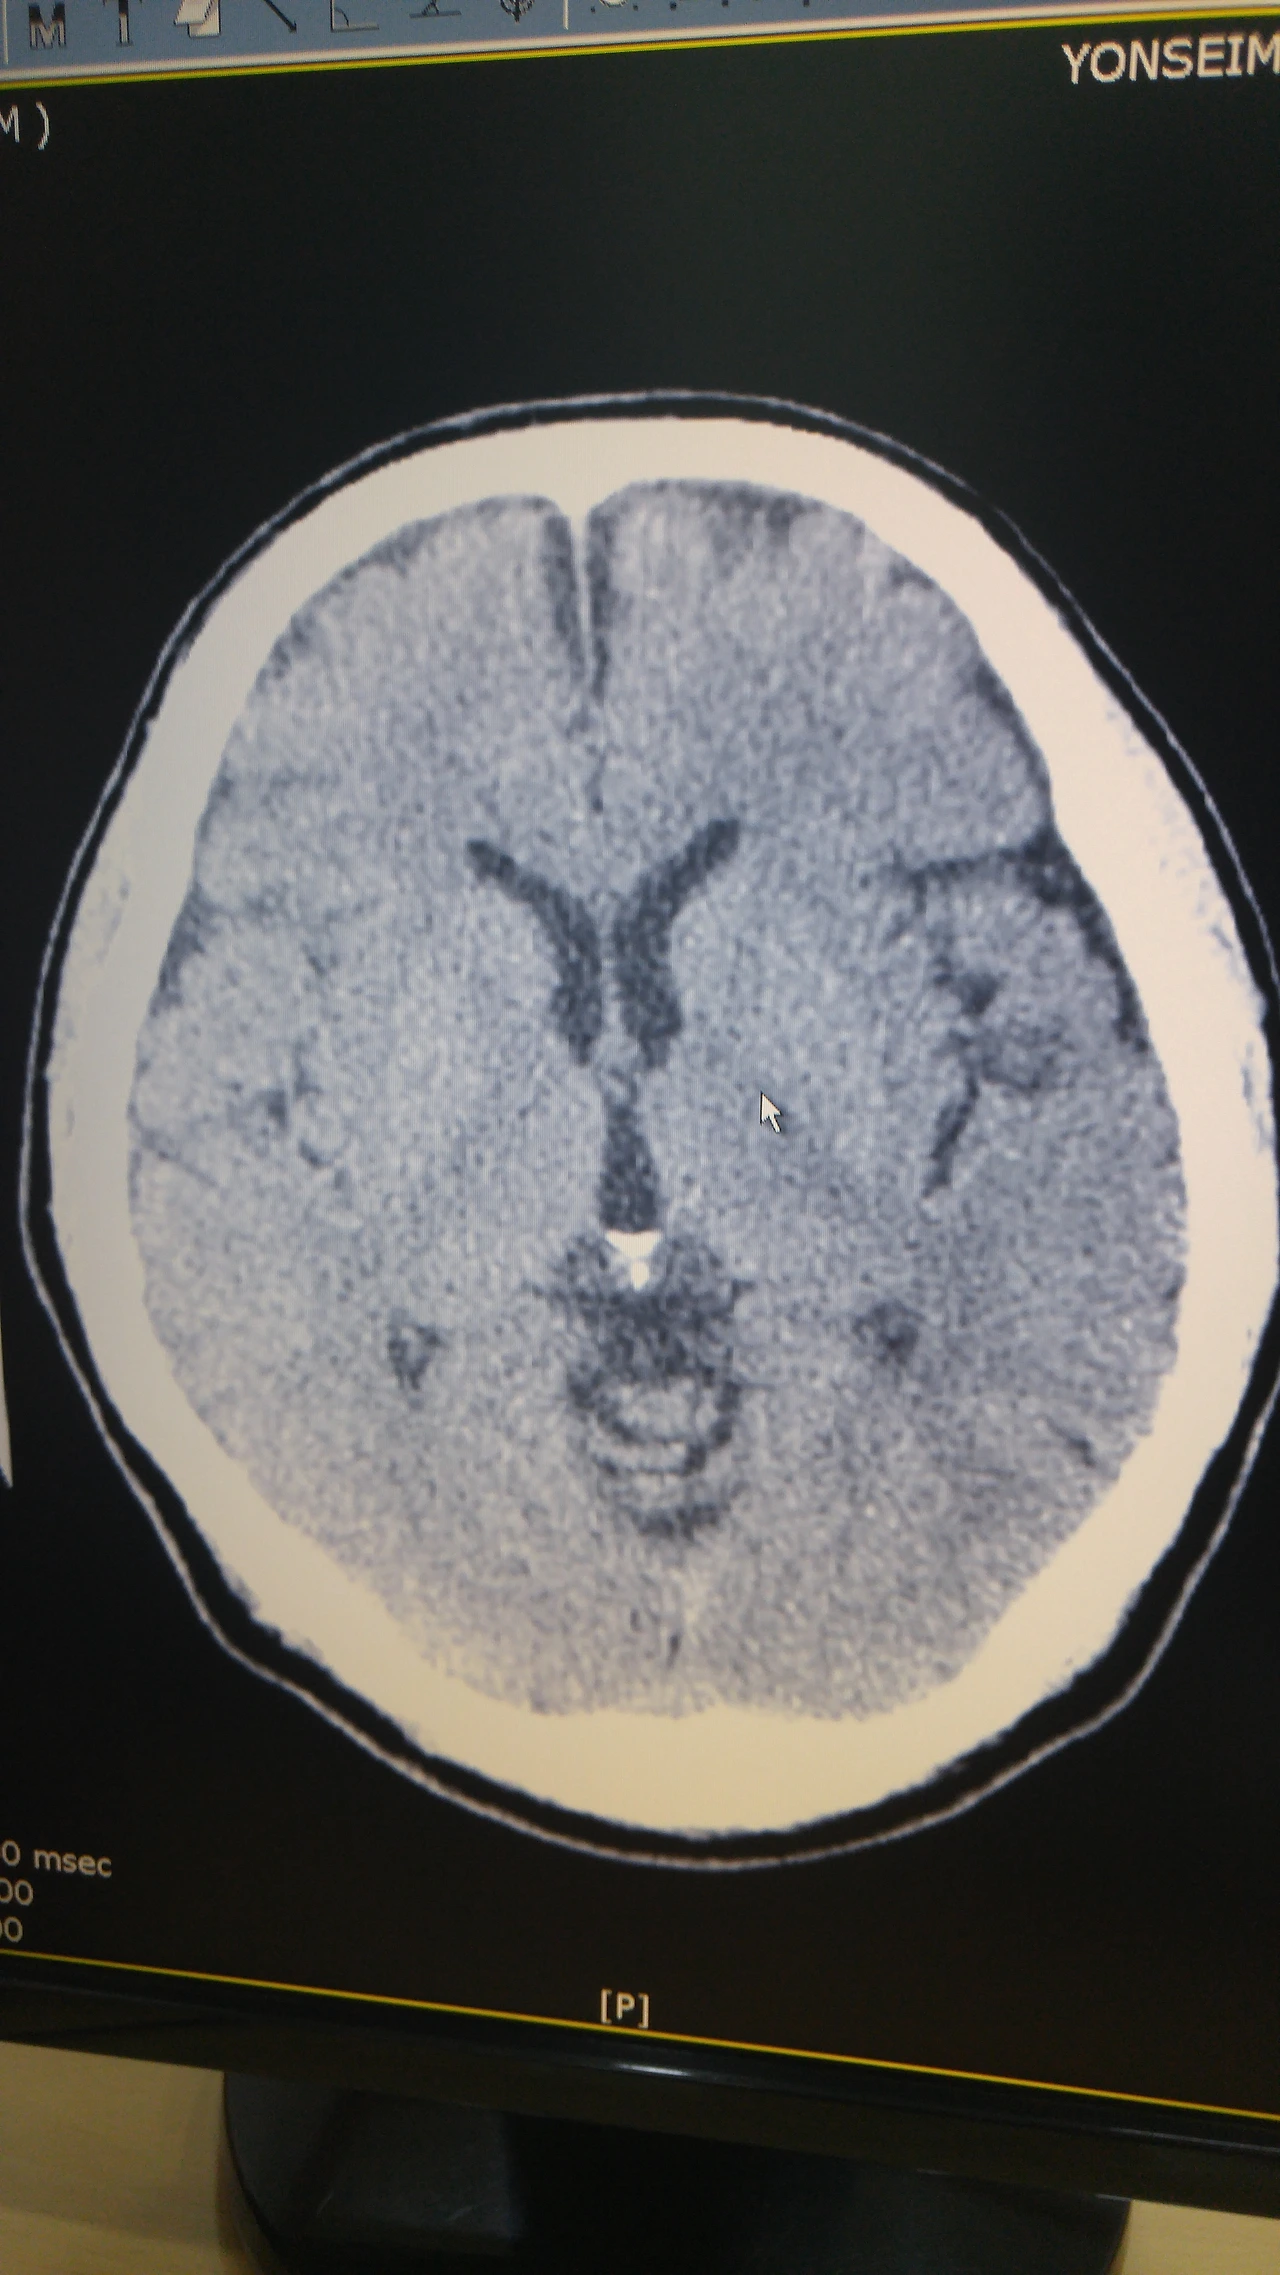

50세쯤 신경과에서 별일 없이 찍어본 뇌 CT

전문의 판독

외곽 흰 테두리 뼈 접한 부위 검은 색은

빈 공간

뇌 부피가 줄어든 거라고

중앙도 일부

타인 청춘 사진 보여 주는데 동일 부위 흰색

뇌가 뼈까지 빈틈 없이 꽉찼더라

내 나이 정상 뇌란다

인지 못 하고 지나간 뇌경색 외엔